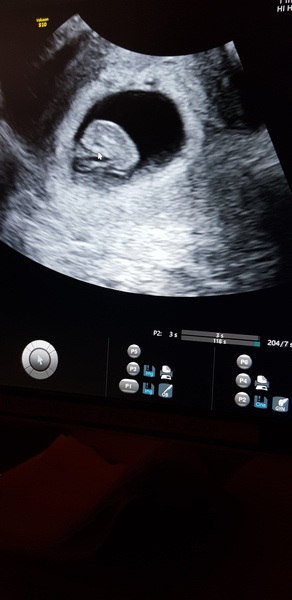

DaisyMay25 · 20/06/2019 20:14

@AstroKate lovely scan! I'm not sure about nub theory but the head is stacked so I'm guessing boy!

AstroKate · 20/06/2019 20:53

Thanks everyone. Good luck to those scanning tomorrow.

I don't understand the nub theory either-have to wait til 20weeks

Lovely scan pic @AstroKate!

AstroKate such a lovely scan picture!

We had early scan last week as i had some cramps....i was 7+5....baby is spot on on the days and we saw lovely heartbeat.....

@Sunshine3105 -lovely scan picture! Xx

@AstroKate congrats on ur scan photos they are lovely. Ive no idea on nub or skull theories tho 🙈